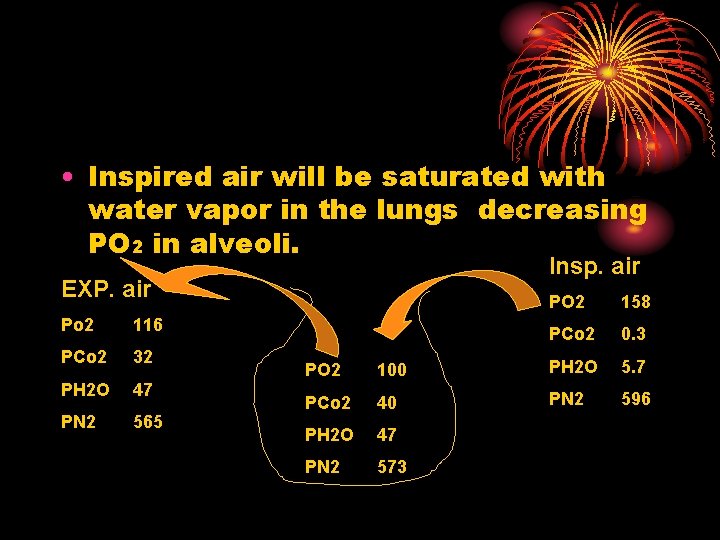

• Inspired air will be saturated with water vapor in the lungs decreasing PO 2 in alveoli. Insp. air EXP. air Po 2 116 PCo 2 32 PH 2 O 47 PN 2 565 PO 2 158 PCo 2 0. 3 PO 2 100 PH 2 O 5. 7 PCo 2 40 PN 2 596 PH 2 O 47 PN 2 573